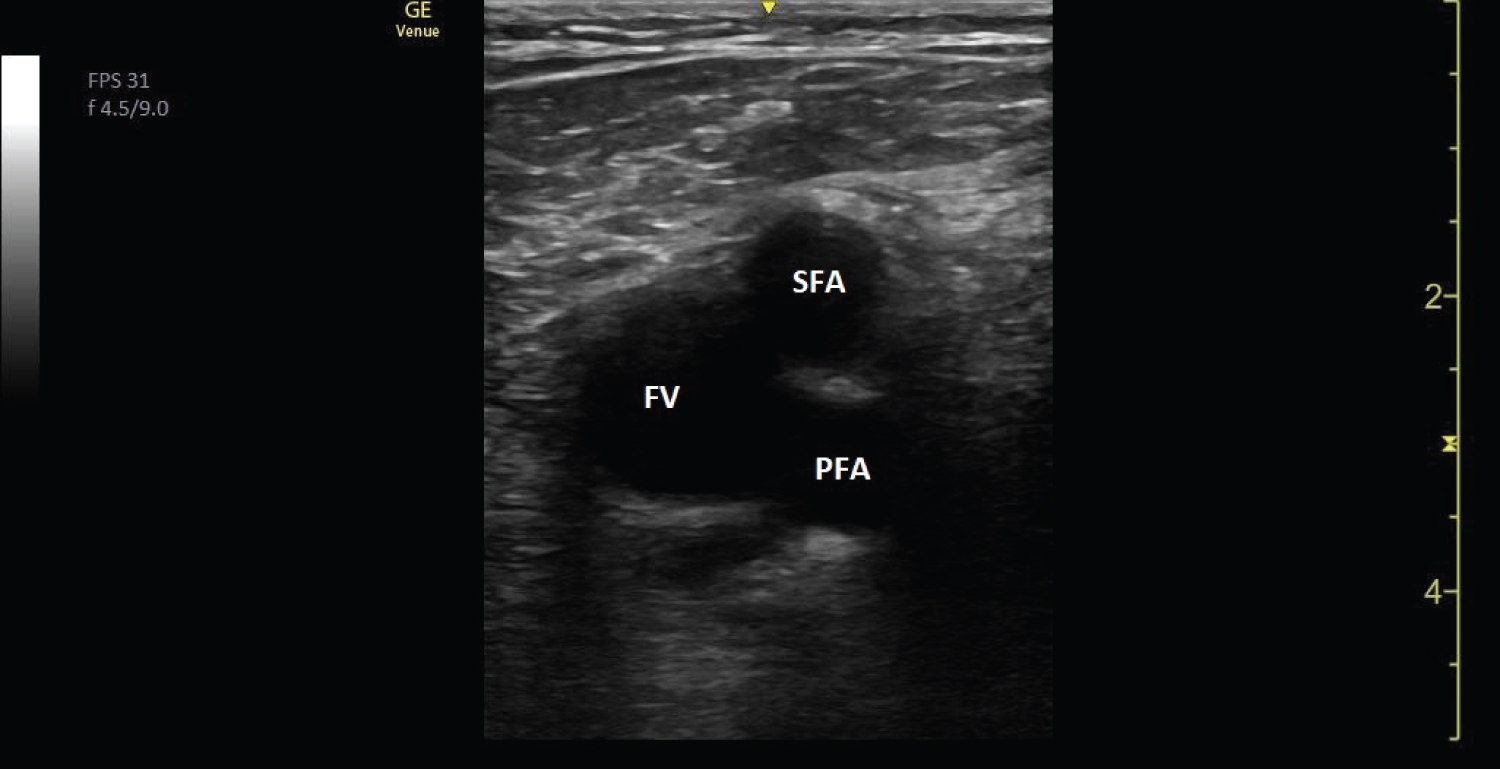

With the patient in the supine position, the examined leg slightly rotated externally, and with a gentle flexion of the knee, ECUS was performed by compressing the deep veins, starting with the common femoral vein (Figure 1), and compressing for every centimeter, continuing just proximal to the division of the popliteal vein (Figure 2). The linear transducer (3-12 MHZ linear transducer, GE Venue) was used for the examination and was placed transversely, perpendicular throughout the examination [12].

Figure 1: Ultrasound image showing the left femoral vein (FV) and the superficial (SFA) and profound (PFA) femoral artery. View Figure 1